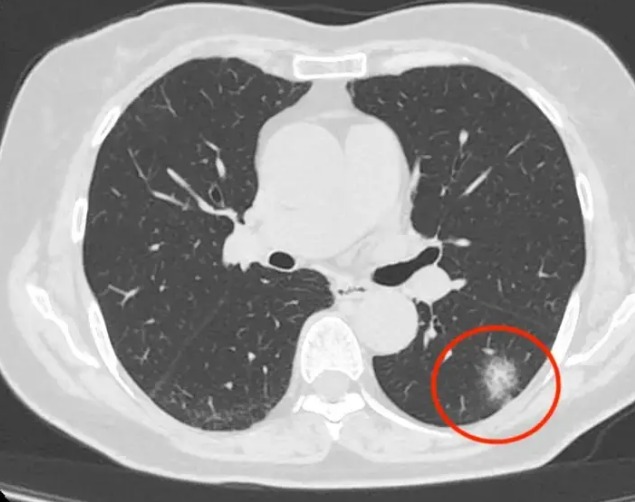

肺部结节是指直径不超过3厘米、圆形或椭圆形、不透明、周围有肺实质的肺部病变。在胸片或CT扫描中,结节像一个小的白色丘疹。

大多数结节是良性的。炎性假瘤、错构瘤、结核瘤、真菌感染、硬化性肺细胞瘤、局灶性出血等会引起肺结节,这些结节大多不会发展为肺癌。

肺结节根据其性质、大小和密度进行分类。那么,哪些肺部结节的风险较高?

见大小:大于1.5cm的实性结节或大于8mm的混合毛玻璃结节为高危结节,必须给予足够重视并定期复查。